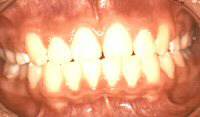

Việc điều trị chỉnh hình răng mặt sớm sẽ:

- Giúp xương hàm phát triển hài hòa với khuôn mặt thẩm mỹ hơn.

- Giúp hài hòa khớp cắn giữ a hai xương hàm.

- Giúp răng mọc đúng vị trí.

- Hạn chế chấn thương các răng nhô ra phía trước.

- Sắp xếp các răng ngay ngắn lại sớm.

- Sắp xếp các răng ngay lại mà không cần nhổ răng bằng cách nới rộng xương hàm.